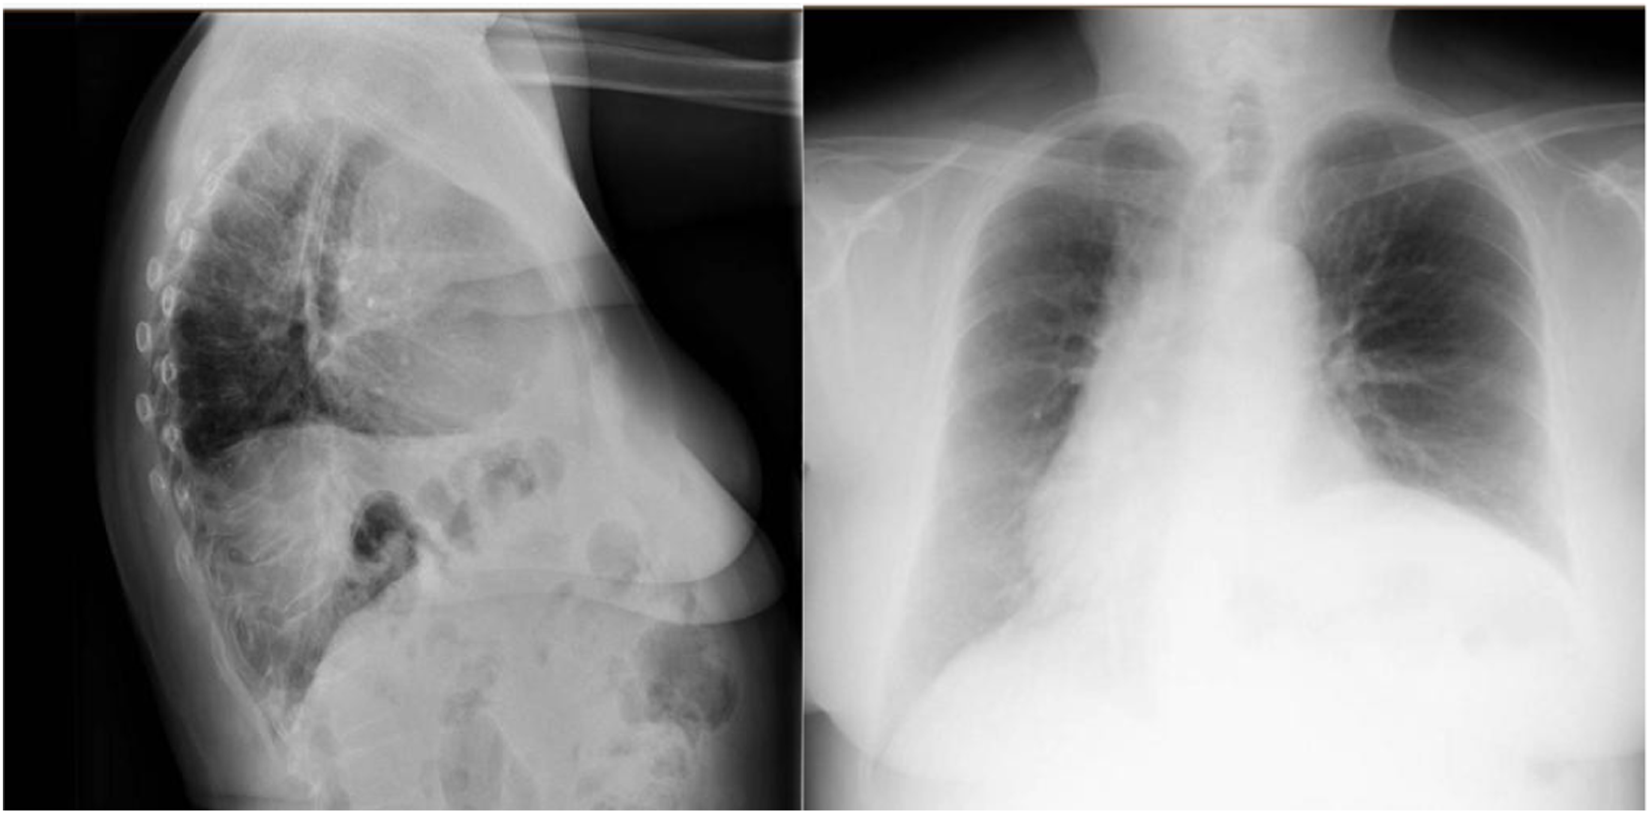

At a six-month follow-up, the patient reported a significant improvement in her quality of life, with improved respiratory function and digestive symptoms. At 12 months, the patient remained asymptomatic and without recurrence. The follow-up postoperative X-ray showing decreased—but not complete resolution of—left hemidiaphragm elevation compared to the preoperative state, which did not show an elevated diaphragm (Figure 4).

FIGURE 4

Postoperative image showing decreased—but not complete resolution of—left hemidiaphragm elevation compared to the preoperative state.